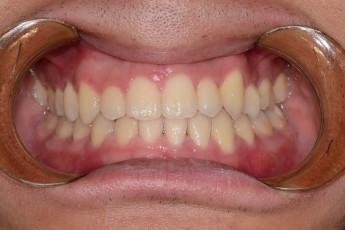

BEFORE & AFTER

- 덧니교정